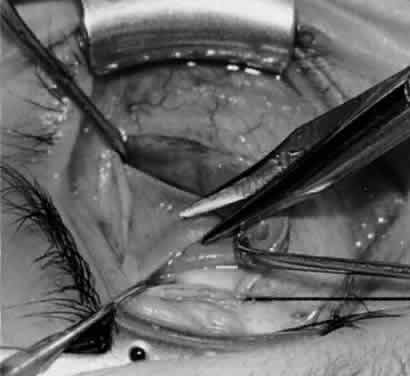

Fig. 11. Sutures are placed into the insertion of the inferior oblique muscle before it is sectioned from the globe for the recession procedure.

Fig. 12. An Aebli scissor is placed beneath the inferior oblique muscle insertion before it is sectioned from the globe.